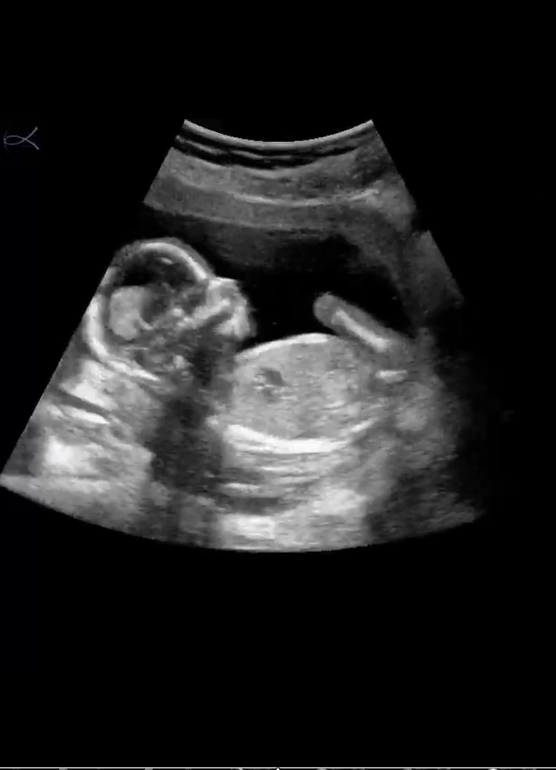

Рассекретили пузожителя ❤️

Пол малышаСегодня ходили с мужем на УЗИ, чтоб определить пол малышика )

Малышку нашу врач посмотрел вдоль и поперёк, сказал все отлично, и носик и губки, и мочевой и сердечко. Тааак она выросла с первого скрининга, такая уже большая стала 🥰❤️

По параметрам мы немного опережаем, по акушерскому сроку сегодня 15.3 нед.а малышка развита по КТР на 16 неделек )

Такая активная, ручками и ножками махала, что то там жевала, точнее глотала ))

Пару раз пнула датчик, врач умилялся а я не а седьмом небе от счастья наблюдала за нашей прелестью ))

Сделала пару скринов с видео нашего Чуда 🥰